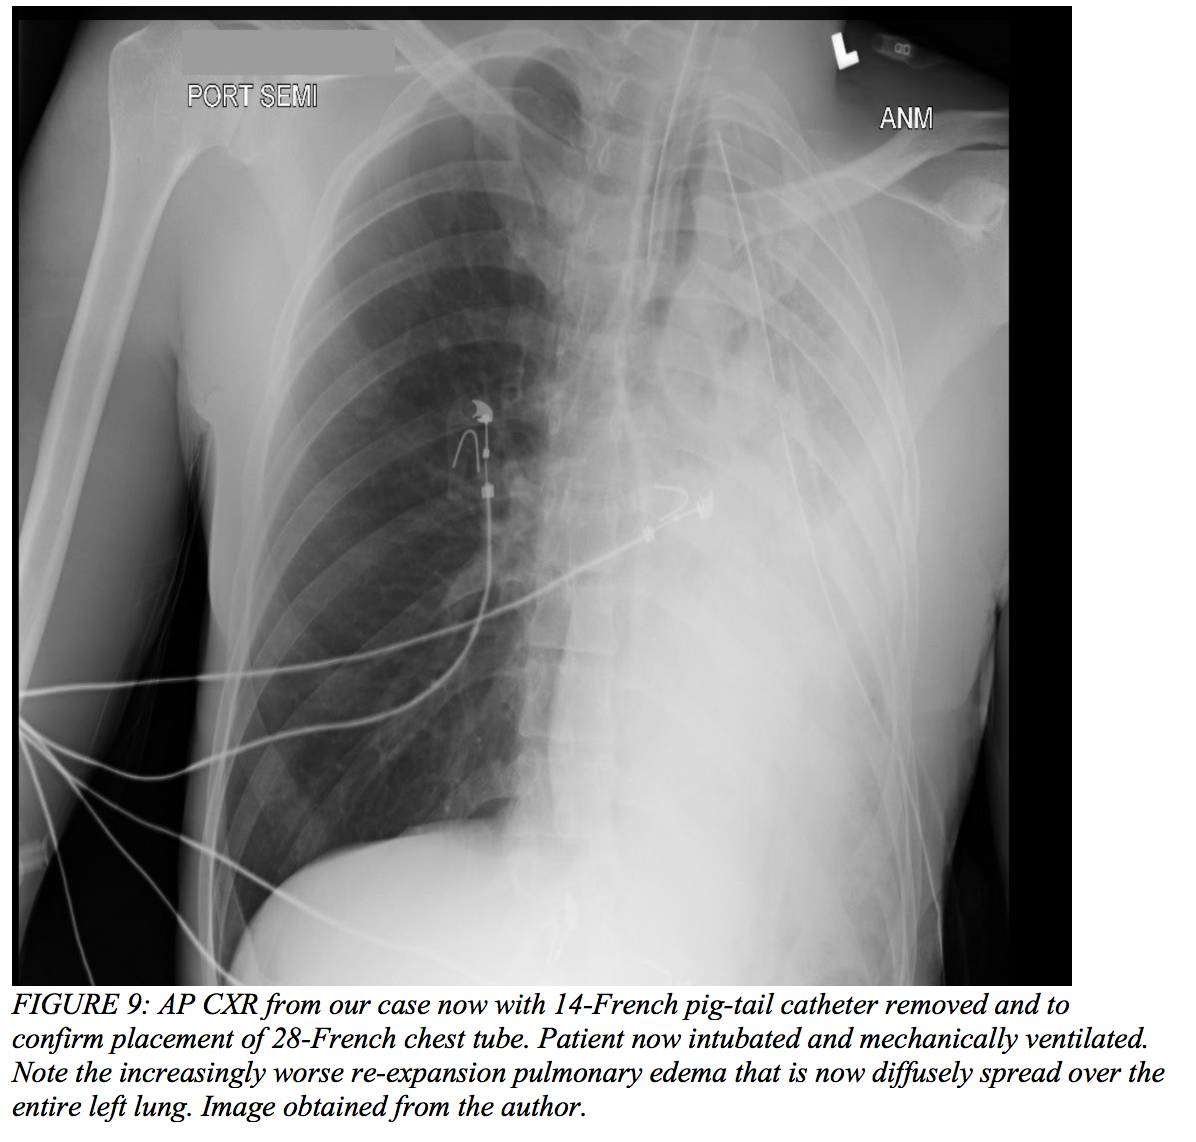

Case Conclusion

After initial imaging displayed a pneumothorax (Figure 7 above), our 39-year-old male had a pig-tail catheter placed successfully (Figure 8 below). However, his dyspnea failed to improve, and he continued to desaturate even when connected to supplemental oxygen via non-rebreather. The decision was made to replace the pig-tail catheter for a 28-French chest tube (Figure 9). His clinical status failed to improve even after this intervention, and he ultimately required intubation due to impending respiratory failure and an evolving pulmonary contusion. The patient was then transferred to the surgical intensive care unit and closely monitored on mechanical ventilation for two weeks. His oxygenation and ventilation improved over time, and he was extubated and subsequently discharged without any further complications.